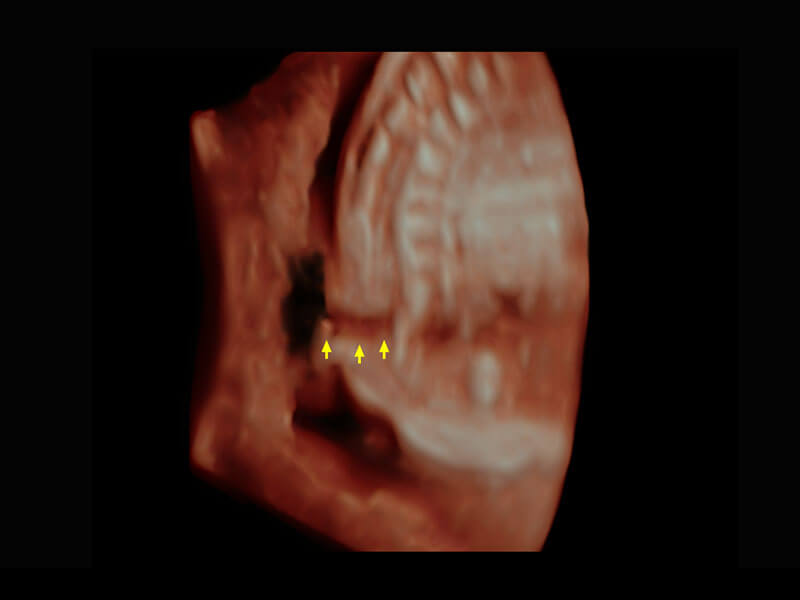

早孕筛查

P60在胎儿早孕期超声筛查中为您带来优异的图像质量。

• 早孕-胎心

• 高分辨率容积成像-早孕胎儿

• 胎儿体循环

• 光影成像-孕囊